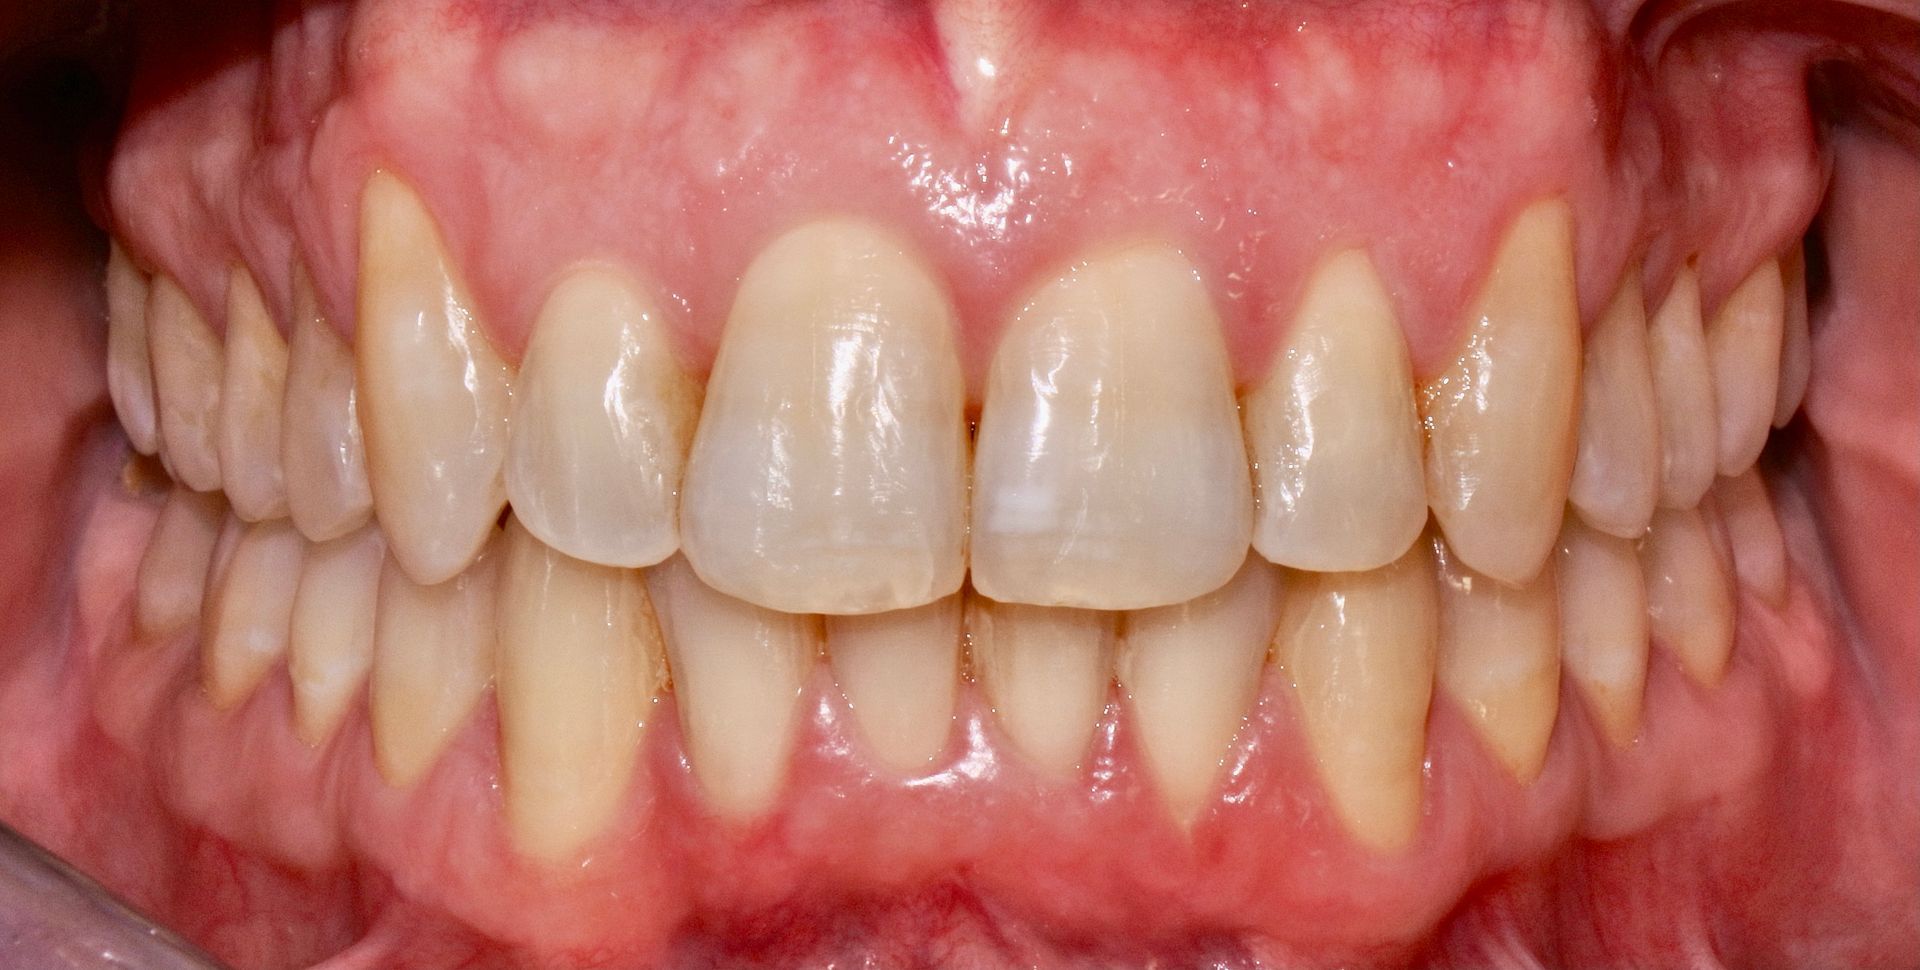

Ciascun singolo movimento migliora il sorriso, in modo delicato.

Le mascherine personalizzate, praticamente invisibili, vanno indossate dal paziente 20/22 h al giorno, consentendo così di poter mangiare e lavare i denti senza problemi.

Questo è l'enorme vantaggio rispetto all'ortodonzia tradizionale, dove i brackets (attacchi) sono fissi sui denti.